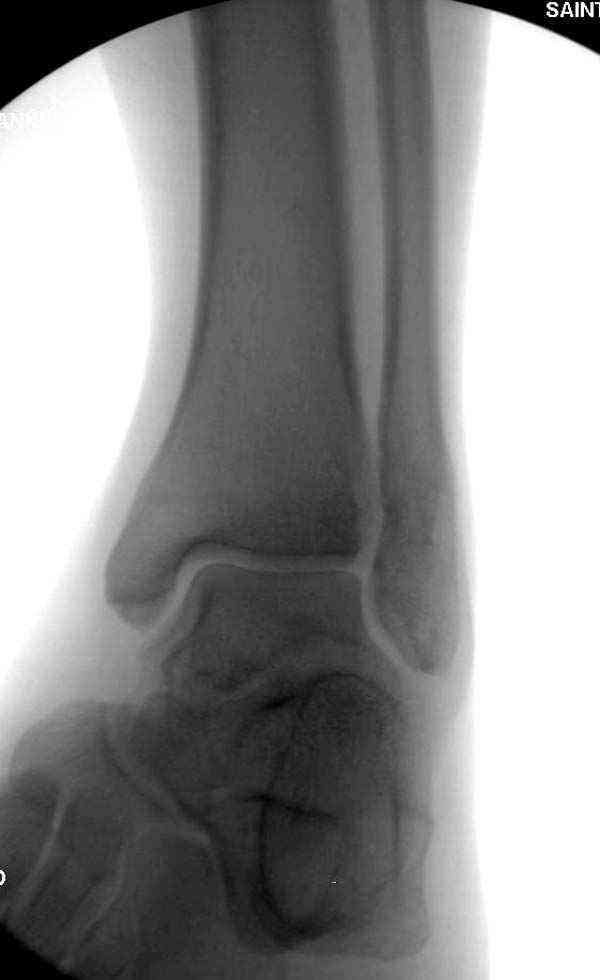

Нет первичных снимков, перелом очень низкий и под большим сомнением диагноз разрыва синдесмоза. Медиальная сторона отрепонирована на "хорошо" и, по-видимому, прорезание проволоки произошло во время операции. Без снимков трудно судить о высоте малоберцовой, а лодыжка находится в варусе. Лагирование получилось, но возле тонких шурупов передне-задний шуруп выглядит немного тяжеловато.

Медиальная лодыжка фиксируется каннюлированными лодыжечными шурупами перкутанно, а неточная репозиция (интерпозиция) является показанием к открытой технике. При больших вертикальных фрагментах нужны противоскользящие медиальные пластины.

Коллеги правы, что при рутинных переломах достаточным бывает обычные снимки с мортизом. А стрессовые рентгенограммы могут уточнить, есть ли разрыв синдесмоза.

Здесь несколько частных случаев: перелом голеностопа со сравнительными снимками и разрыв синдесмоза, а также медиальная Hook пластина.